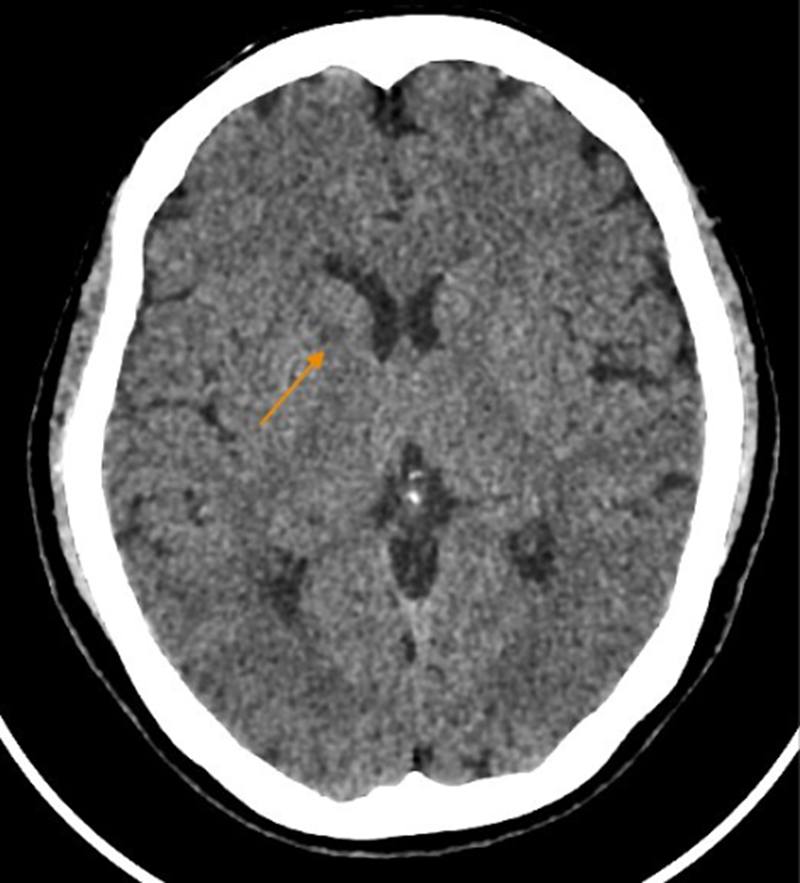

Hình ảnh chụp CT não của bệnh nhân C có dấu hiệu bất thường (ảnh: BSCC).

Khi sự việc xảy ra, kết quả thăm khám cho thấy bệnh nhân huyết áp tăng 150/90 mmHg, cơ lực nửa người trái giảm rõ, nếp mũi má mờ, méo miệng, phản xạ gân xương giảm. Chụp cắt lớp vi tính sọ não ghi nhận xơ vữa vôi hóa động mạch cảnh trong hai bên đoạn xoang hang và động mạch đốt sống. X-quang tim – phổi cho thấy cung động mạch chủ giãn nhẹ kèm vôi hóa. Siêu âm Doppler mạch cảnh phát hiện mảng xơ vữa vôi hóa tại xoang cảnh trái; siêu âm tim cho thấy hở nhẹ van động mạch chủ.

Bệnh nhân được chẩn đoán đột quỵ nhồi máu não giờ thứ 9, tăng huyết áp và được chuyển tuyến điều trị chuyên khoa.